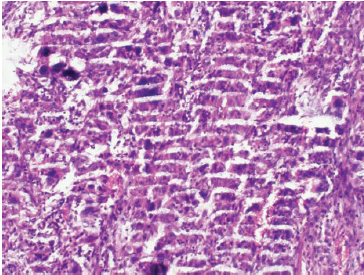

八、组织发生裂隙破碎或崩脱——问题分析及补救措施

技术资料图片8

1、脱水处理不当。需重新脱水。

2、有透明剂残留。应增加浸蜡时间,重新包埋。

3、由于脱水机和透明剂的影响,组织变硬发脆。可调整脱水程序。

4、材料太硬或太大。可脱钙,分开包埋。